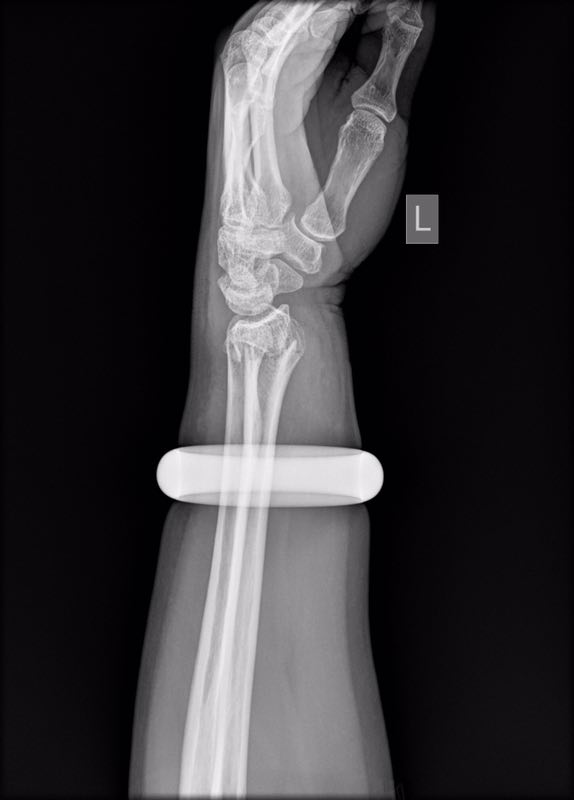

25日早上,57岁的王女士早晨买完菜回家时不慎滑倒,情急之下她用左手撑地,很快手腕就肿了起来。邻居听说后,让她赶紧去做做按摩,结果越按越痛,越肿越厉害。下午她找到武汉市第一医院骨科门诊,拍片发现左手桡骨远端骨折。

此时,王女士手腕上戴的玉手镯深陷肉里,无法取下。手镯卡住腕部,不但会加重局部肿胀,还会越勒越紧导致肢体坏死。管床医生石晨尝试用肥皂水、润滑剂等方法取镯,都没能成功。